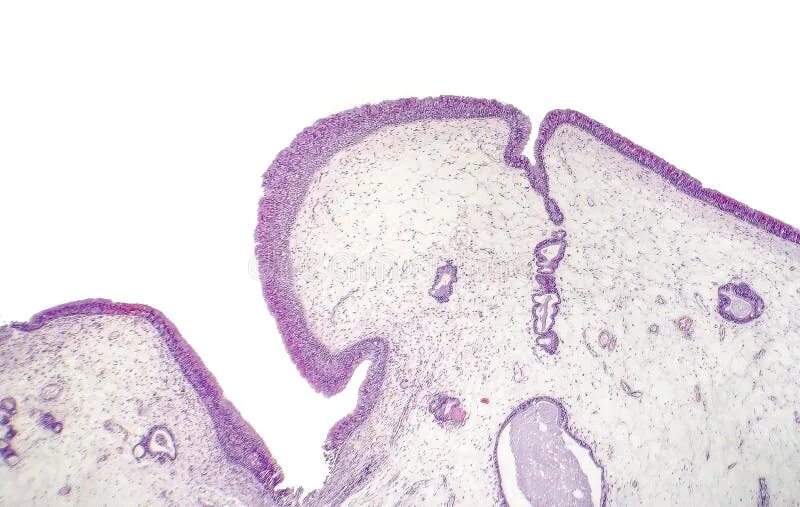

Гистология нос